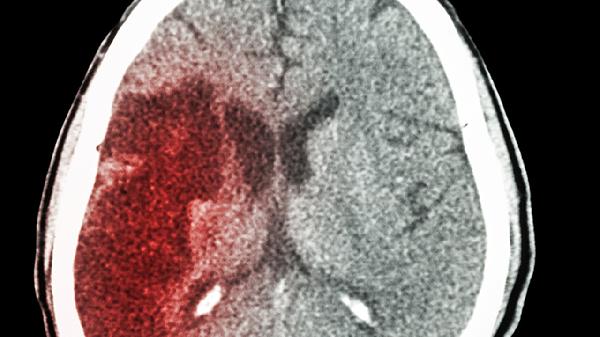

早产儿脑白质发育不成熟,合并窒息史者易发生脑室周围白质软化,表现为运动协调性差。需在新生儿科进行亚低温治疗等干预,后期持续监测发育里程碑,必要时采用神经节苷脂钠注射液等药物辅助治疗。